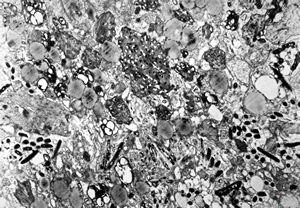

Whipple disease